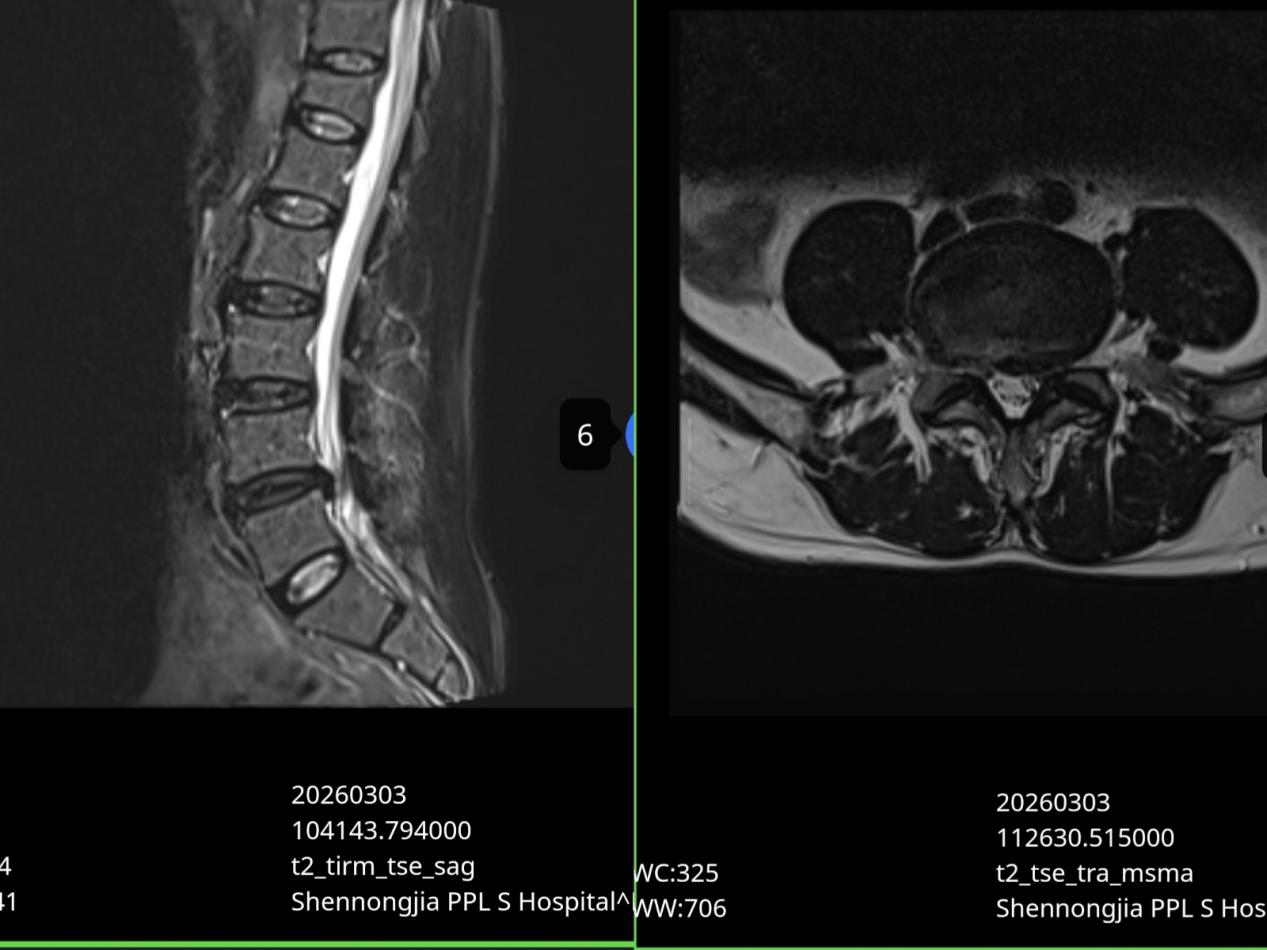

患者周某,因腰痛伴随左臀部及下肢放射性疼痛、麻木前来就诊,症状严重到影响正常行走和生活。影像学检查明确诊断为腰椎间盘脱出,神经根受到明显压迫,从医学指征上看,已达到传统开放手术的标准。然而,患者对手术创伤、风险和漫长的恢复过程深感恐惧,坚决拒绝接受开放手术。

针对患者的特殊情况和对治疗的期望,中医康复科团队进行了细致的评估和方案讨论,最终制定了超声引导下脉冲射频治疗的微创方案。该方案旨在避免破坏脊柱正常结构、不损伤神经血管的前提下,精准地对受压神经进行干预。